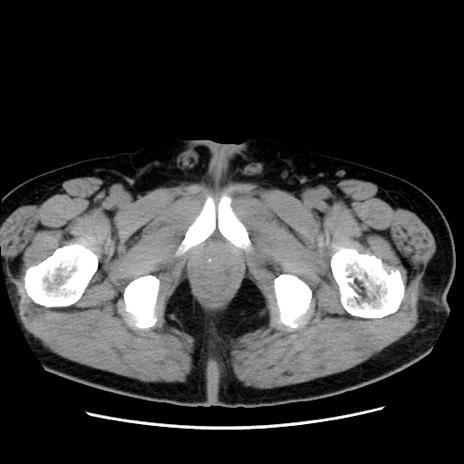

症例16(横断像)

【症例】 70歳代男性

【主訴】 腹痛、嘔吐

【現病歴】 約1ヶ月前より間欠的に腹痛と嘔吐あり、当院消化器内科を受診したところCTで多発する肝臓のLDAを指摘され、精査中であった。以降は消化器症状は安定していたが、2日前より嘔気と腹痛があり、同日より排便・排ガスが消失した。改善認めず、 本日、救急外来を受診した。

【既往歴】 大腸ポリープ切除後。

【身体所見】意識清明・会話良好、BT 36.3℃、BP 127/80mmHg、 P 80bpm、腹部:膨満あり、平坦・軟、上腹部正中および下腹部正中に圧痛あり、反跳痛なし、筋性防御なし。

【データ】WBC 7200、CRP 0.77